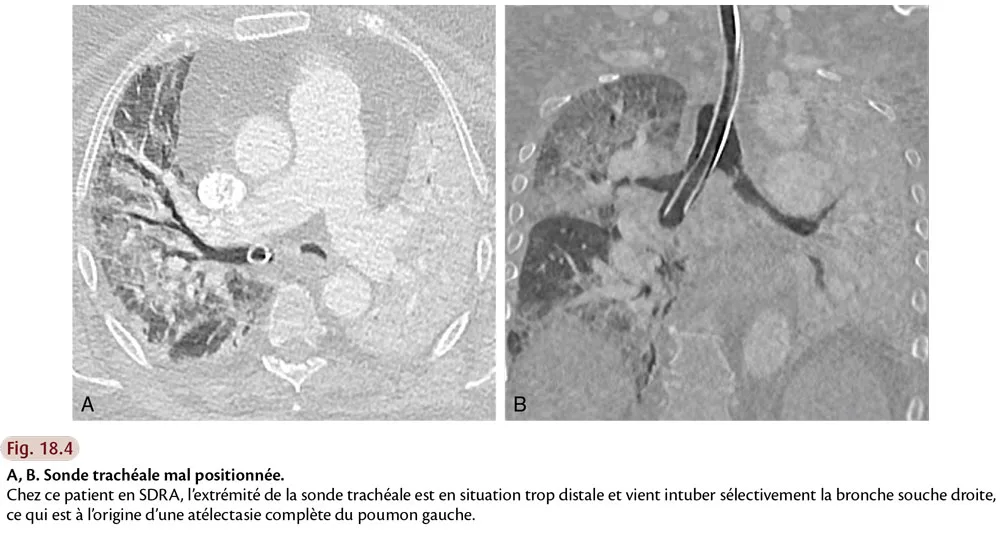

Devant un poumon de réanimation, le radiologue doit, dans la mesure du possible, essayer d’identifier un pattern TDM, et rechercher en particulier un aspect de PIA, mais aussi d’éventuels diagnostics différentiels (fig. 18.3). Il doit également traquer les comorbidités : pneumothorax, pneumomédiastin, emphysème sous-cutané, embolie pulmonaire, mauvais positionnement des cathéters, drains ou sondes (fig. 18.4).

Fig.18.4